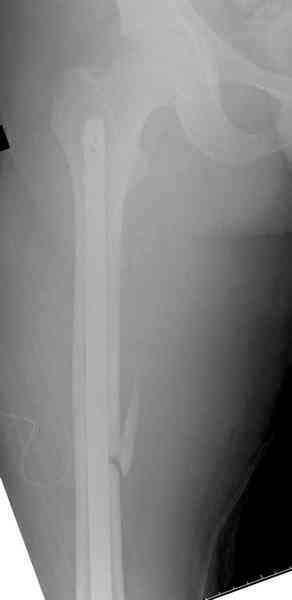

Предыдущей сменой до 4:00 утра по поводу открытого перелома бедра, тибиал плато, пилон и надколенника сделана операция.

Пострадавшему 21 г., травма скоростная, после I&D с расширением раны, на бедре сделана операция ретроградным интрамедуллярным штифтом, остеосинтез с частичной резекцией надколенника и ушивание собственной связки.

На голень наружный фиксатор, рану на бедре ушили (рана была изнутри кнаружи всего 2 см). По протоколу травматических больных, до операции обследован ангиографически, (у больного дистально не смогли определить пульсацию) сосудистый хирург подтвердил проходимость на всем протяжении магистрального сосуда нижней конечности по снимкам ангиограмм.